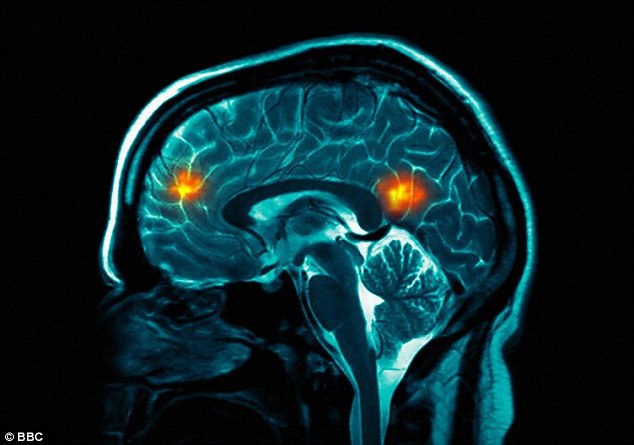

Keeping track: There has been an increase in the number of child brain cancer sufferers, and the ONS has also spotted a rise in brain tumours

もっているトラック:小児脳ガン患者の数の増加があった、そして、ONSは脳腫瘍の増加も観測した